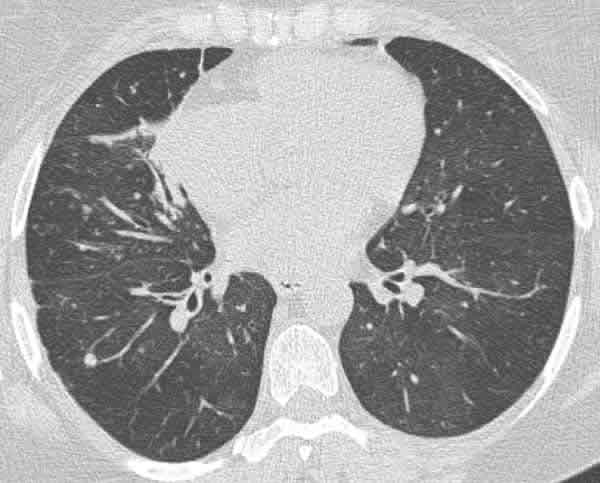

Fig. 3: Corte basal con TCAR que muestra alguno de los nódulos pulmonares, atelectasia parcial de lóbulo medio y signos de perfusión en mosaico.